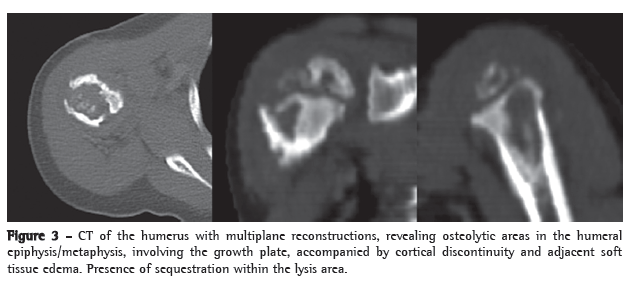

A 21-month-old boy, born in São Paulo, presented with fever and mild functional impairment of the right upper limb. The child had daily episodes of fever (> 38°C), predominantly at night. One week prior, the child had started presenting pain upon palpation and upon movement, as well as limited movement of the right arm. The mother stated that the boy had no history of local trauma. An X-ray of the right upper limb revealed a lytic lesion of the proximal epiphysis/metaphysis, with ill-defined borders, surrounded by a halo of reactive bone sclerosis, periosteal reaction and soft tissue edema (Figure 1). Magnetic resonance imaging revealed areas of abnormal marrow signal and soft tissue edema with highlighting of the infected marrow by the contrast medium-signs consistent with osteomyelitis of the proximal humerus (Figure 2). The patient received cephalosporin for 10 days in an outpatient setting. On day 8 of the antibiotic therapy, the child came to our facility due to fever and persistent pain.

Complementary examinations revealed the following: leukocytes, 8,200 (9% rods and 66% neutrophils); erythrocyte sedimentation rate, 32 mm/h; C-reactive protein, < 6.0 mg/L; normal urine sediment; normal chest X-ray; and strongly positive PPD result, 18 mm. A CT scan of the humerus revealed multiple lytic lesions in the proximal region of the humerus, involving the epiphysis, the metaphysis and the proximal diaphysis, as well as cortical discontinuity and adjacent soft tissue edema (Figure 3).

Lytic and sclerotic bone lesions with periosteal reaction characterize the radiographic lesions. In the case described here, the CT findings in the epiphysis, the metaphysis and the diaphysis were consistent with previous descriptions in young patients. Older children usually present only metaphyseal changes.(4)